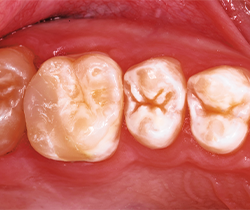

After occlusion is adjusted and restorations are finished and polished with OptraPol polishing cups and points (Ivoclar Vivadent), final radiographs and photos are taken to demonstrate the radiopacity of the material, the ideal interproximal contours and sealed margins, and its monolithic, void-free qualities (Figs. 16-20).

Fig. 18 Fig. 19